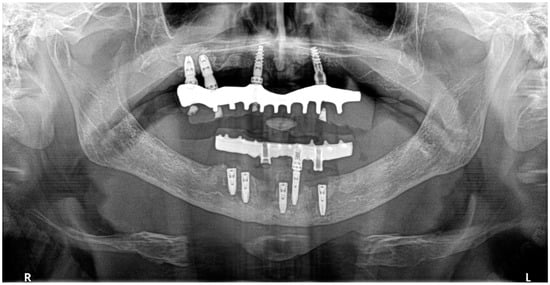

2. Case Description